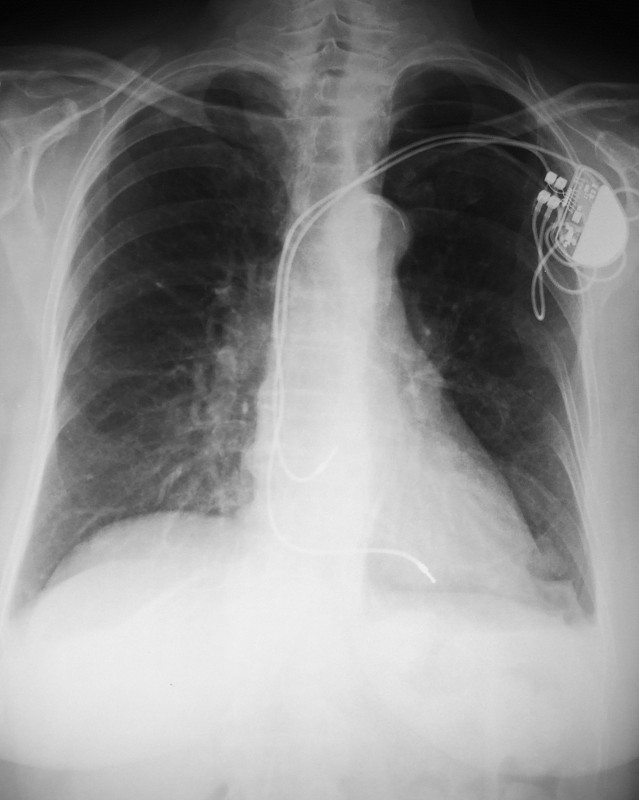

心脏起搏器详情

JPG

Pacemaker详情

SVG

起搏器详情

JPG